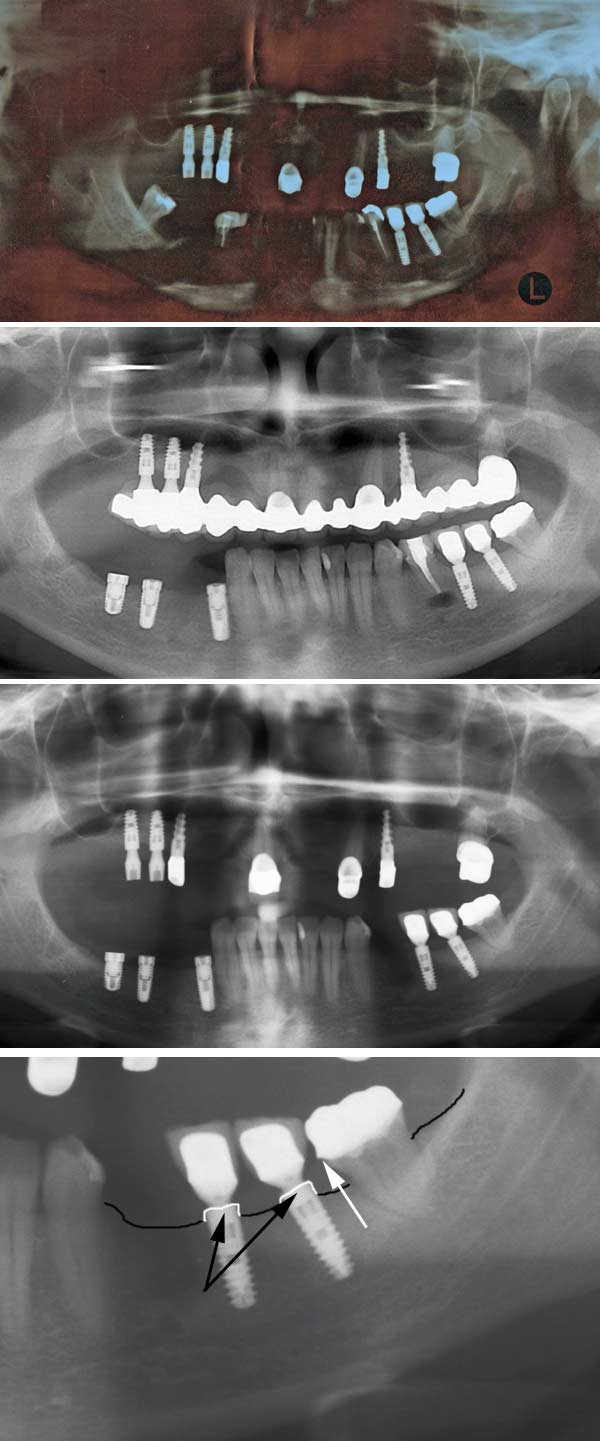

Habe mir Ihre Röntgenbilder angesehen und chronologisch zusammen gereiht. Das erste Bild kann ich leider nicht gut beschreiben – zu dunkel.

Was auffällt ist die leider häufig klassische Chronologie des Zahnes 35, schlechte WB -> schlechte WSR -> Zahnextraktion.

Bei der Arbeit im Oberkiefer handelt es sich um eine Teleskop Arbeit – soweit im Rö beurteilbar schön gemacht.

Im Unterkiefer links scheint die eine Krone undicht zu sein (weißer Pfeil) – mehr dazu im Video Krone.

Negativ anzumerken ist der Einsatz vieler verschiedener Implantatsysteme (Ankylos, Straumann, ?), das macht die prothetischen Versorgungen nicht unbedingt leichter und billiger.

Die Ankylosimplantate wurden zu wenig tief gesetzt – mehr dazu in dem B] – laut Hersteller sollten diese Implantate 1-2 mm unter Knochenniveau gesetzt werden. Grund: bei Ankylos ist die Implantatschulter zusätzlich aufgeraut, das kann wenn die Implantate außerhalb des Knochens stehen leichter zu Entzündungen führen – zurzeit ist aber kein Knochenabbau zu sehen.

Eine Engmaschige Kontrolle (1/2 jährlich) wäre ratsam. Die Kieferhöhlen, Kiefergelenke, parodontal Zustand sind soweit beurteilbar ok.